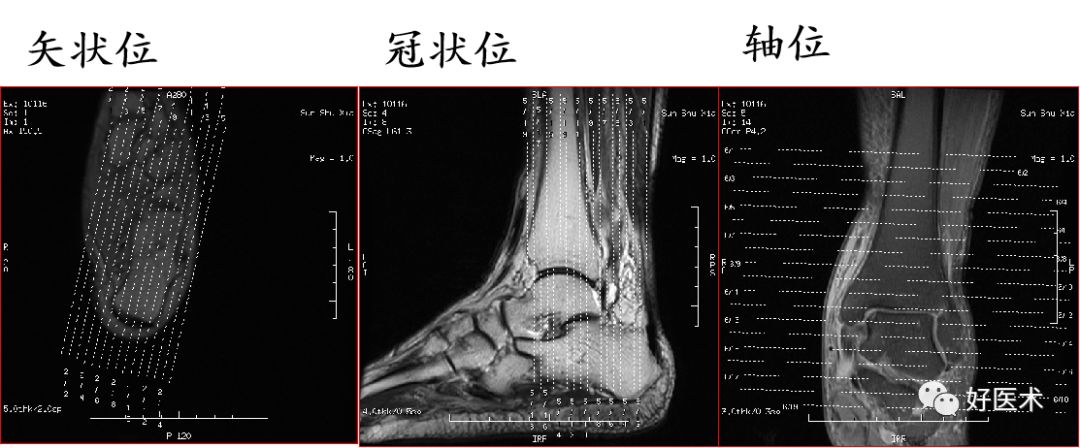

一、解剖和扫描方法

扫描定位